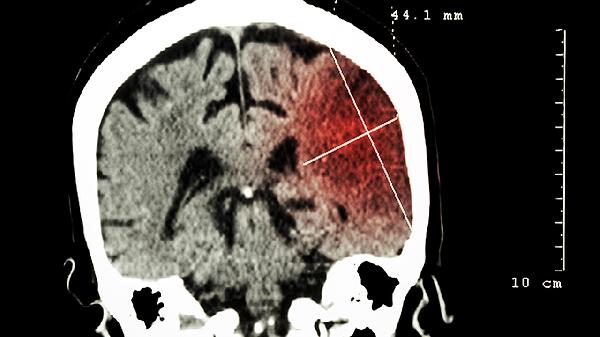

1、缺血性中风

脑得生丸可用于缺血性中风恢复期的治疗,常见症状包括半身不遂、口眼歪斜、语言不利等。该药中的川芎、当归等成分有助于改善脑部血液循环。使用时应配合医生指导的康复训练。常见同功效药物有血栓通胶囊、脑心通胶囊等。